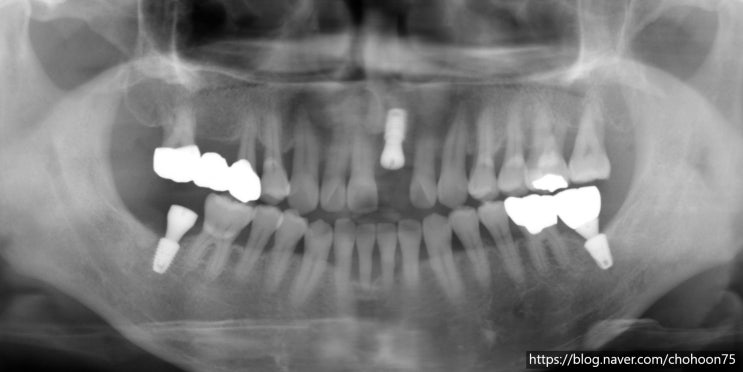

[조훈치과] 싱글 임플란트 치료 증례 (9년 경과)

안녕하세요. 조훈 치과입니다. 자연 치아를 상실하게 되었을 때 조훈 치과에서는 자연 치아를 살리는 치료...